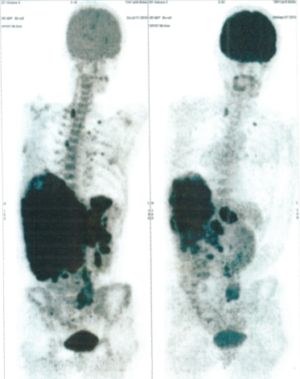

Below are some of the cases, from more than 80 cases we have treated so far with good results. When reading the PET/CT scans, the picture on the left is before treatment, and the picture on the right is after treatment. The intensity of black represents the activity of the cancer, but some black areas are not cancer: brain, heart, radioactive urine in bladder. For the heart, the intensity of black depends on the number of hours of fasting: if more than 10 hours, the heart is not even black, but if fasting is less than 6 hours, it is very black. The intensity of black in the brain can be variable in different scans depending on the brain activity at the time of the scan. The intensity of black in the radioactive urine can also be variable due to the hydration of patients and the time of injection of diuretic.

CASE NO: 1

(HEPATOCELLULAR CARCINOMA + STOMACH CANCER)

A middle-aged women who is very thin and very weak, can hardly walk, lying in bed most of the time. She saw a cancer specialist in a top hospital who discovered that she had massive hepatocellular carcinoma, and another cancer in the stomach. Given that hepatocellular carcinoma is incurable and stomach cancer is very difficult if not impossible to cure without surgery, she was told that nothing could be done for her. She came to ask us to help her. After just 4 treatment, the hepatocellular carcinoma went into remission, and the stomach cancer (arrow) became less active. Until today, more than 6 months later, the hepatocellular carcinoma is still in remission.